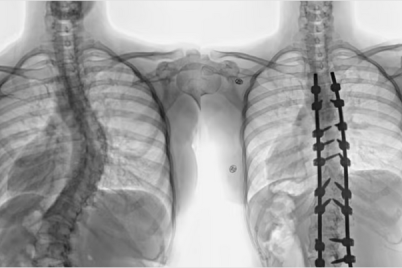

نجح أطباء جراحة المخ والاعصاب والعمود الفقري والأشعة التداخلية في مستشفى الملك فهد التخصصي ببريدة، بإجراء تدخل طبي نوعي، لإنهاء...